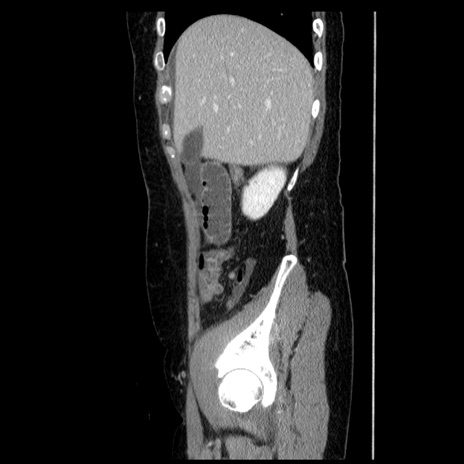

症例6(矢状断像)

【症例】50歳代女性

【主訴】下腹部痛

【既往歴】卵巣癌術後(8年前に当院で卵巣摘出)

【身体所見】 意識清明、腹部:平坦、腸蠕動音→、やや硬、下腹部自発痛・圧痛あり、反跳痛あり、筋性防御なし。

【データ】WBC 16000、CRP 0.01